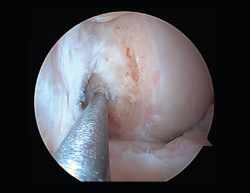

Las principales causas secundarias a errores técnicos son la malposición de la plastia y el tensado excesivo. La radiografía permite ver la localización de los túneles e implantes, así como la RM visualiza las partes blandas implicadas, pudiendo identificar posibles pinzamientos de la plastia –escotadura intercondílea, síndrome del cíclope (Figura 9), síndrome de la contractura infrapatelar(22) (Figura 10)–.

La cronología tras la cirugía es también importante. Durante los 3 primeros meses tras la intervención podemos tratar satisfactoriamente rigideces menores con rehabilitación, antiinflamatorios no esteroideos (AINE) y manipulación. Más allá de los 4 meses, se recomienda desbridamiento artroscópico. No se recomienda la manipulación bajo anestesia sin una liberación articular artroscópica del tejido cicatricial. El desbridamiento artroscópico incluye la retirada de tejido cicatricial, grasa de Hoffa, liberación cuadricipital de la cara anterior femoral y de los recesos laterales, y ocasionalmente liberación de retináculos patelares si la movilidad patelar fuera insuficiente(23).

Figura 9. Cíclope, tejido fibroso interpuesto en la cara anterior de la plastia y que produce pinzamiento de la misma en extensión de rodilla.